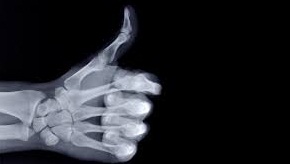

What are X-rays?

- They can pass through most substances including soft tissues of the body but not through bones and most metals.

These are x-rays on the lower end of their range (10-11 – 10-8 m) and have more penetrating power than normal x-rays. They are capable of penetrating flesh but are absorbed by bones.

Soft X-rays

They are on the upper end of the range and are less penetrative. They can only penetrate soft flesh and can be used to show malignant growth in tissues.

1. Medicine - X-ray photos called radiographs are used as diagnostic tools for various diseases. They are also used to treat cancer in radiotherapy.

4. Security - Used in military and airport installations to detect dangerous metallic objects i.e. guns, explosives, grenades etc.